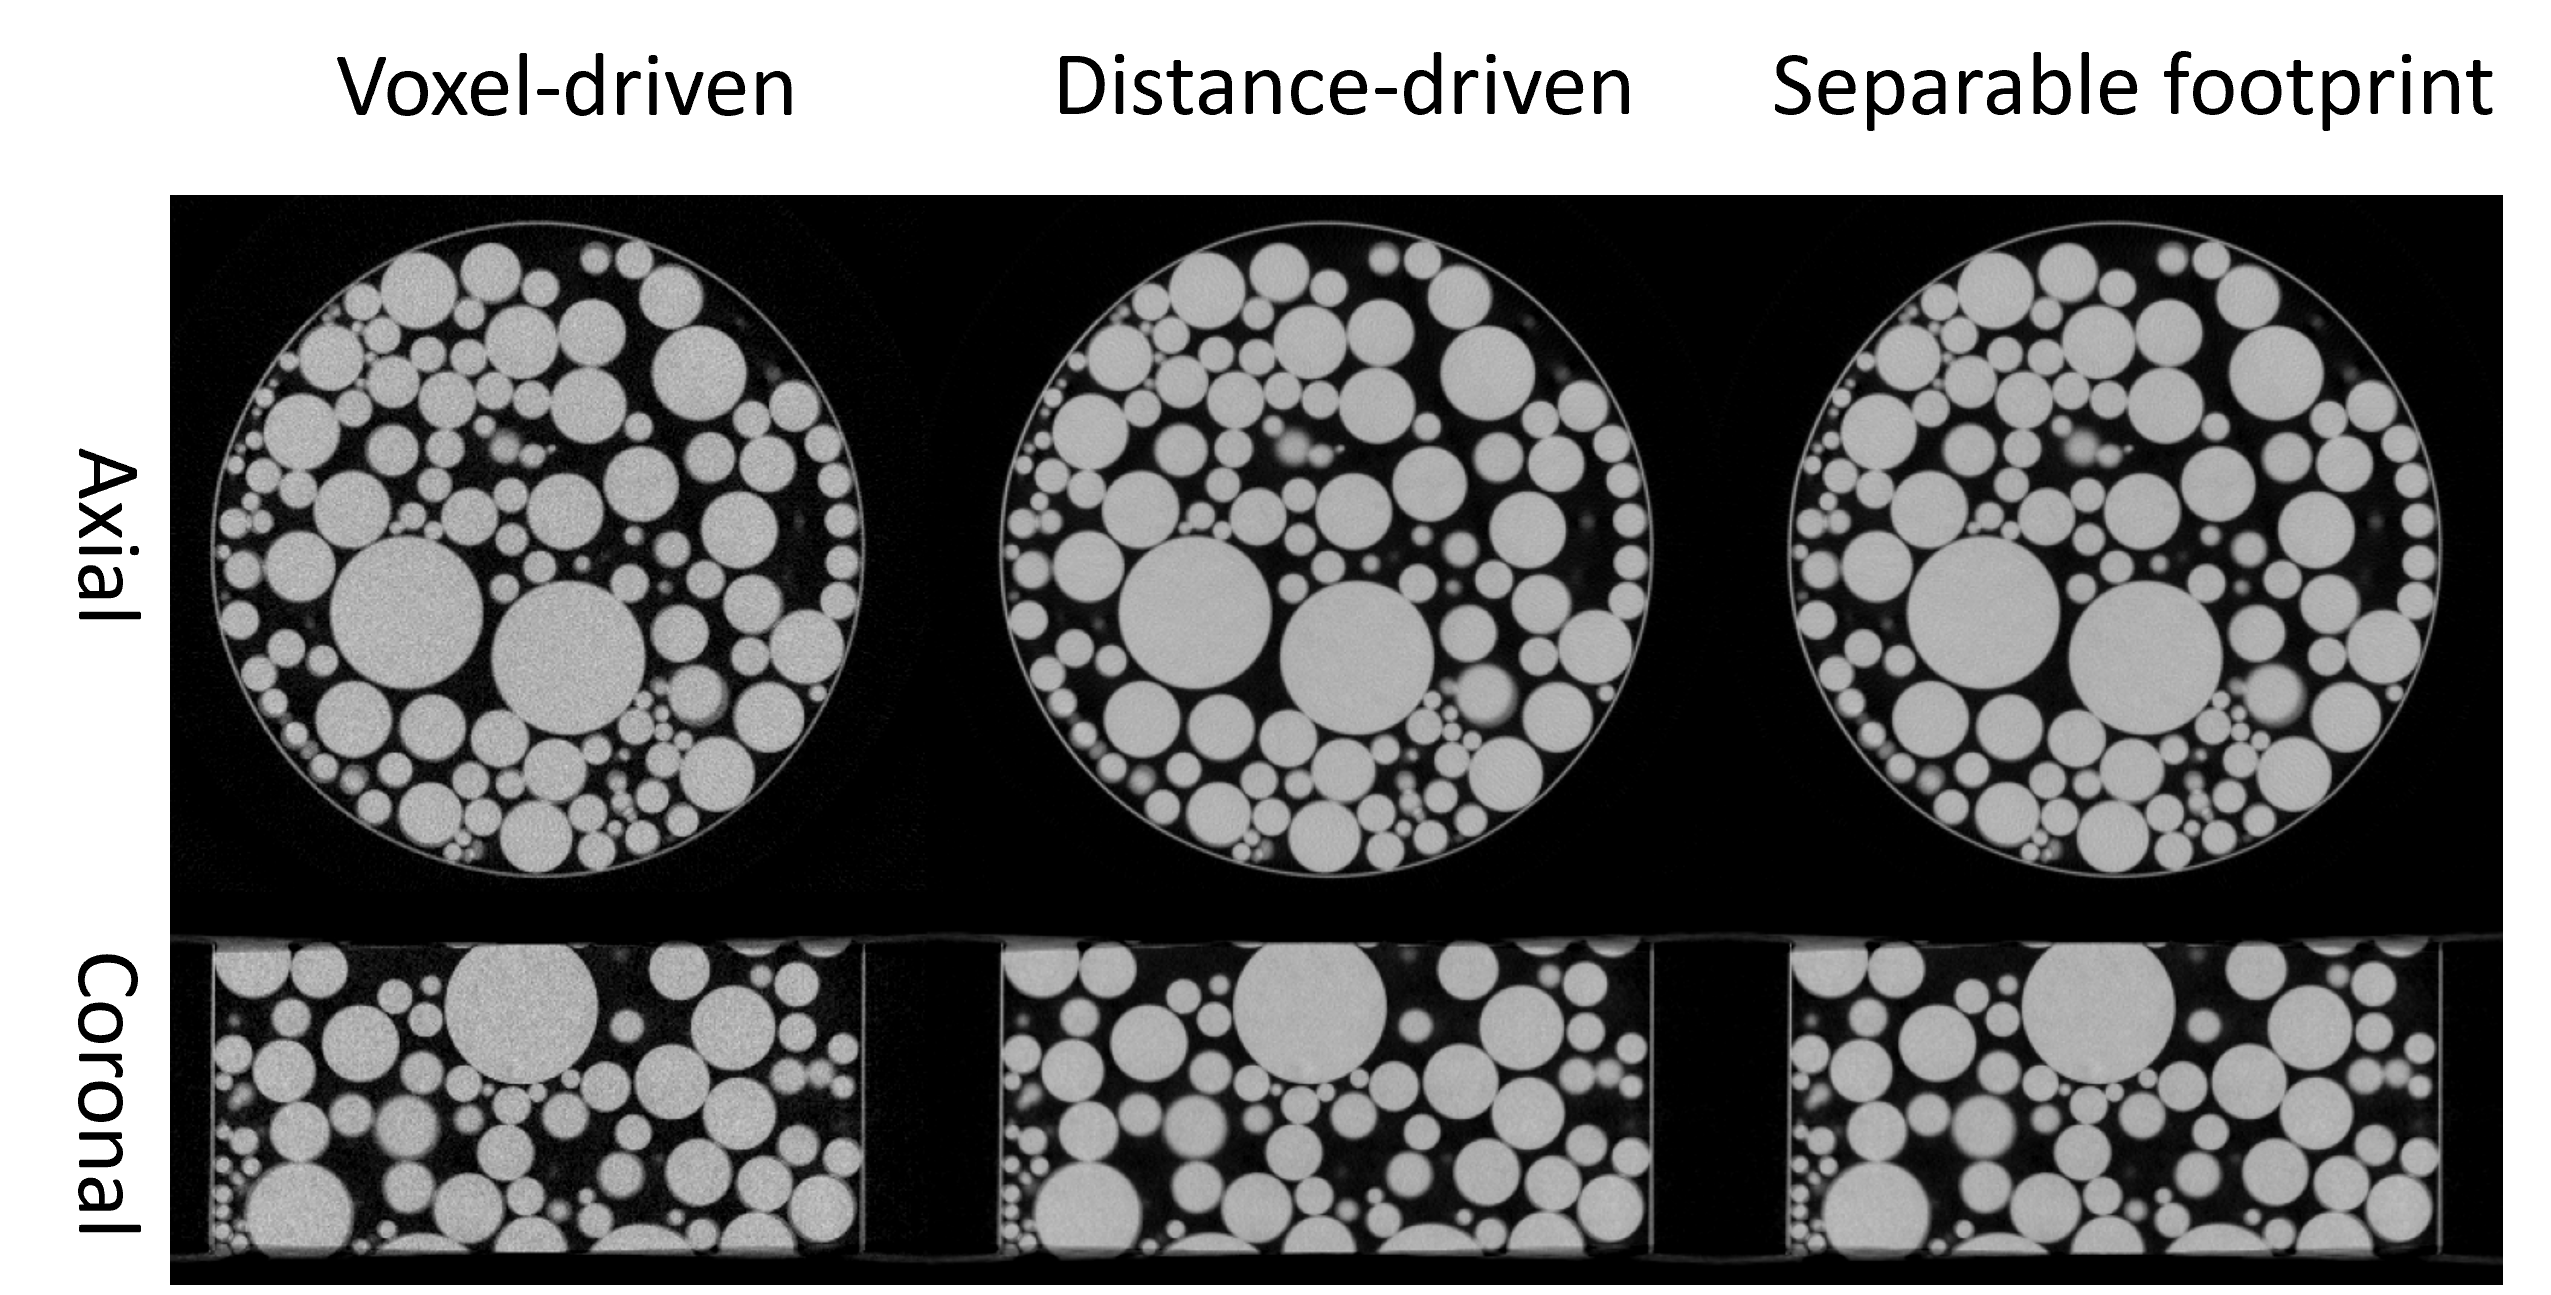

Figure 4: FBP reconstruction using the top-layer projections from a dual-layer CBCT system wiht different projector algorithms.

We validated the CTorch projector for both circular and non-circular geometries using physical x-ray bench data. A plastic ball phantom was scanned on a laboratory benchtop CBCT system equipped with a dual-layer flat-panel detector[CareView560DE]. The two-layer projections were reconstructed separately using the FBP algorithm under a 3D circular geometry assumption. Fig. 5 presents the reconstruction results for the top layer using different projectors. Each projector accurately depicts the ball shape with sharp edges, demonstrating the high geometric accuracy of the CTorch circular-scan projector. Fig. 5 shows the bottom-layer results. When the projections are backprojected under the circular geometry assumption, geometric distortions are noticeable, particularly around the ball edges. These distortions may arise from misalignment of the detector pixel grids between the two layers. However, by shifting to a non-circular geometry model that incorporates a 0.4°0.4\degree in-plane detector rotation, the distortions are substantially reduced. This validates the accuracy of the CTorch non-circular projector and highlights the importance of flexible geometry descriptions for processing nonideal physical projection data.